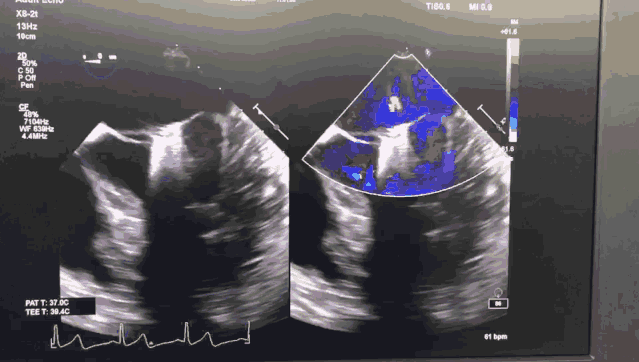

今日手术转播的导管操作时间仅用8分钟,一次性成功。患者术后即刻效果满意,二尖瓣反流从极重度减少到轻中度,未出现二尖瓣狭窄,肺动脉高压从重度降为正常,手术效果良好。

图2 ValveClamp术后经食道心超